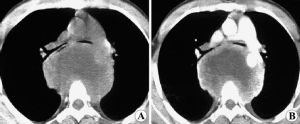

神經節細胞瘤,發生於神經節細胞的腫瘤,好發於第三腦室、顳葉和額葉等部位。神經節細胞瘤(ganglion cell tumors)發生於神經節細胞的腫瘤,好發於第三腦室、顳葉和額葉等部位。